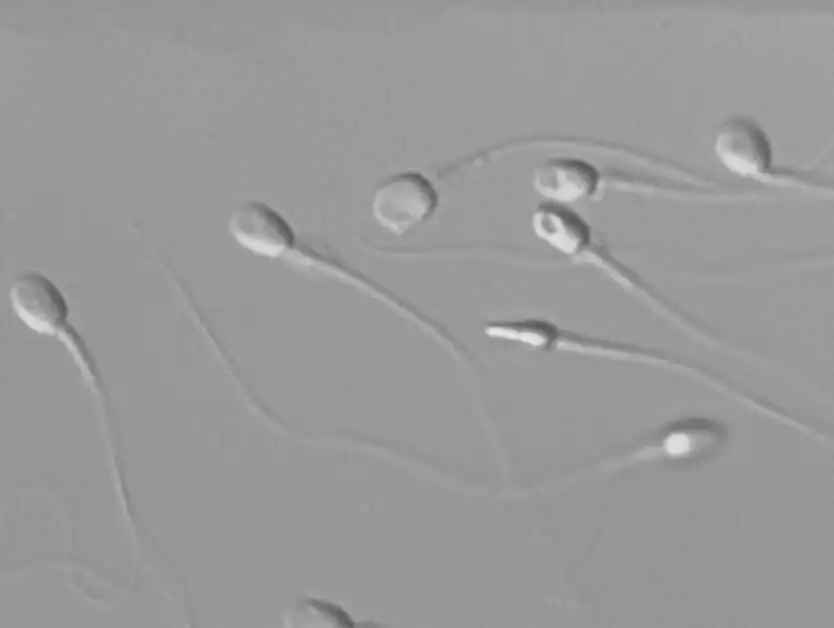

The brightness of the field of view when looking through the eyepiece has been significantly improved. You can observe oocytes and sperm more clearly than ever before. Nikon’s high-quality objectives enable observation of colorless and transparent oocytes and sperm by adding relief-like shading.

IMSI observation

The 60X and 100X objectives allow for clear identification of fine structures, making them ideal for IMSI.

Vacuoles in the sperm head can be observed (100X objective)

Image courtesy of: Fujita Health University

Nikon Advanced Modulation Contrast (NAMC) observation

The direction of contrast can be adjusted by rotating the modulator in the objective. Plastic dishes can be used.

A sperm in the pipette can be clearly observed.